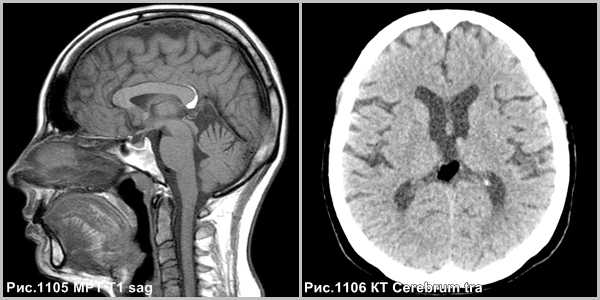

МРТ, Т1-ВИ sag Перикаллезная липома

При КТ и МРТ липома визуализируется в виде объемного образования по характеристикам соответствующего жировой ткани. Дифференциальную диагностику проводят с внутричерепным дермоидом или тератомой, липоматозной трансформацией опухоли (ПНЭТ, эпендимома, глиома), тромбированной мешотчатой аневризмой.

Липома на МРТ головного мозга

Магнитно-резонансная томография позволяет подробно изучить любые мягкие ткани организма. Метод часто применяют для диагностики патологий головного мозга. На снимках видны особенности кровообращения, структура тканей. Чаще всего МР-сканирование головы назначают при подозрениях на новообразования. Метод информативен как при злокачественных, так и при доброкачественных образованиях. Липома на МРТ головного мозга отчетливо видна, как и раздвигаемые ею близлежащие ткани. По результатам сканирования врачи могут определить локализацию образования, размеры, степень влияния на окружающие структуры.

МРТ головного мозга покажет липому?

Магнитно-резонансная томография отражает любые изменения в мягких тканях данной области. МРТ имеет большую диагностическую ценность, в том числе для обнаружения липомы головного мозга. Жировое образование на снимках имеет характерные черты:

- форма любая;

- четкие контуры;

- перифокального отека нет;

- масс-эффект отсутствует;

- не проникает и не разрушает соседние структуры.

При наличии сосудов или кальцинатов внутри липома неоднородная, что заметно при МР-сканировании.

Образование дает выраженный гиперинтенсивный сигнал, который полностью исчезает при исследовании с подавлением жировой ткани. Изучение строения головного мозга по поводу липомы предпочтительно на оборудовании с высоким разрешением. При выполнении данного условия можно заметить места пересечения новообразования с нервами и сосудами. Усиление сигнала с помощью контрастного вещества позволяет с высокой степенью точности изучить вены и артерии и на ранних этапах выявить предвестники инсульта.